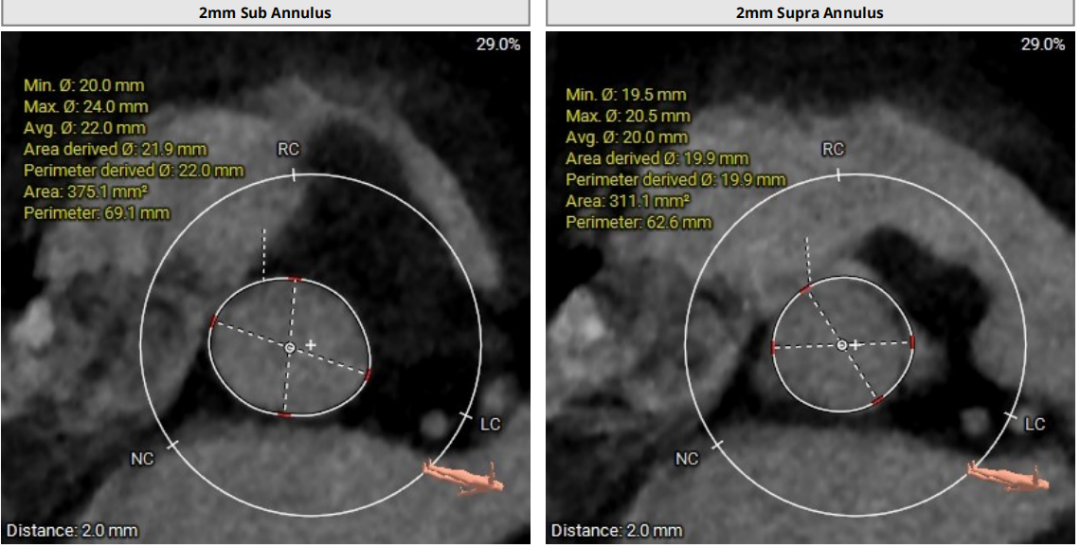

术前CT评估

①Type1二叶瓣,瓣环较小,无窦较大,左右窦有明显瓣叶融合脊;

②瓣叶增厚,瓣口打开受限;

③整体无钙化,AR为主。

瓣上分析

3) 根据瓣环瓣上测量结果,综合评定不预扩张,预装TaurusElite26瓣膜;沛嘉2代输送器非常柔顺,有利于跨过扭曲的主动脉弓部;

4) 释放采用左右重合体位,瓣下2mm释放,结合多体位术中进一步评估瓣膜深度;